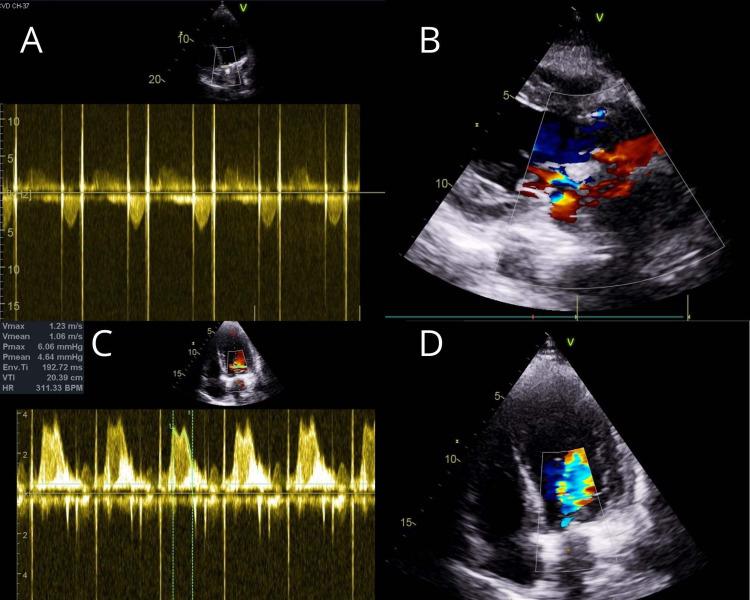

In infective endocarditis, the perivalvular abscess is a known complication with an incidence of more than 22%-29%, but the primary presentation of a healed aortic abscess without any clinical features of infective endocarditis is very rare. These sorts of cases are scarcely documented throughout literature. We present a successful surgical closure of healed perivalvular abscess cavity with aortic valve replacement and mitral valve repair.

在感染性心内膜炎中,瓣周脓肿是一种已知的并发症,发生率超过22% - 29%,但已愈合的主动脉脓肿在没有任何感染性心内膜炎临床特征的情况下首次出现是非常罕见的。这类病例在整个文献中鲜有记载。我们成功地通过主动脉瓣置换和二尖瓣修复对已愈合的瓣周脓肿腔进行了手术闭合。